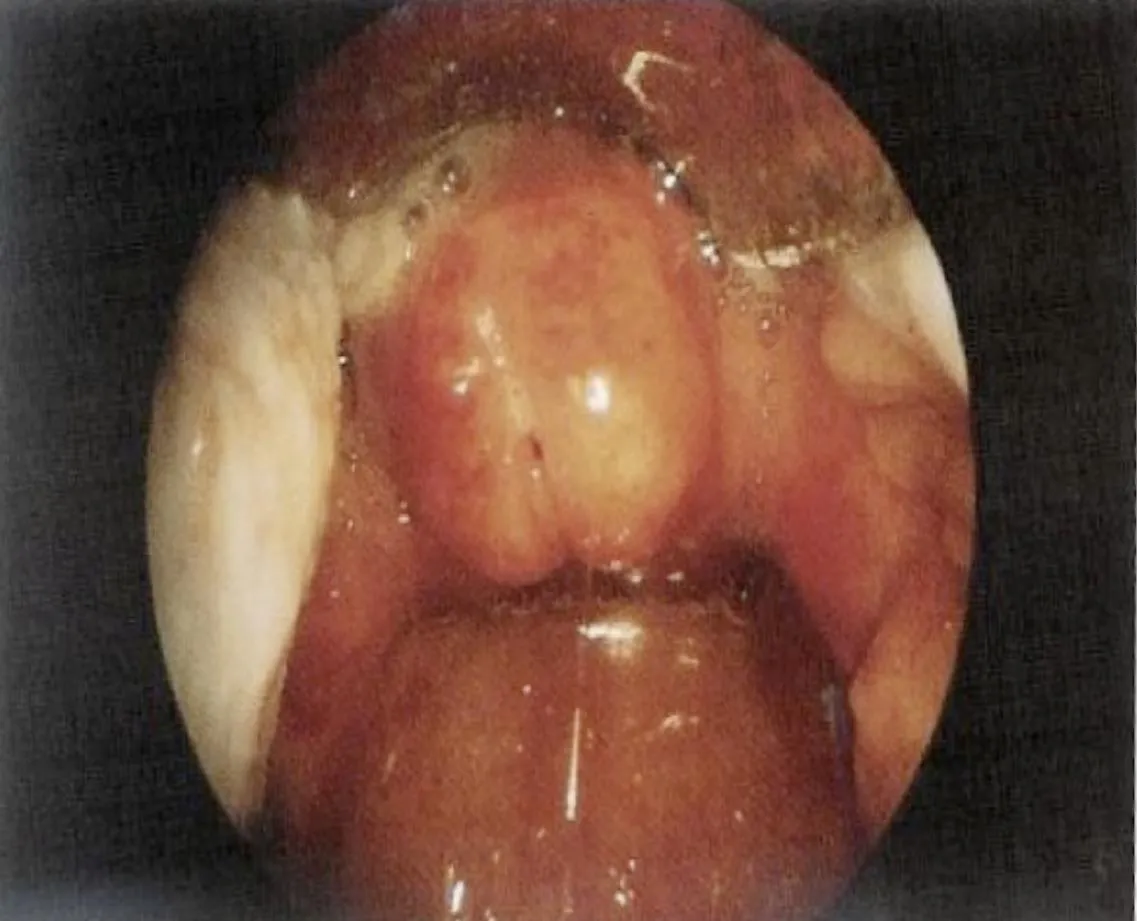

Peritonsillar Abscess

A 25-year-old male presented with a 3-day history of odynophagia and fever, having had an incomplete course of antibiotics 2 weeks prior. - Diagnosis: Peritonsillar Abscess. right side - Definitive Management: - I.V APX, I/D, Aspiration, later tonsillectomy.

A 25-year-old male presented with a 1-week history of odynophagia and fever, managed with paracetamol. He developed severe pain, high-grade fever, and a โhot potatoโ voice.

- Diagnosis: Peritonsillar abscess. right side

- Complications if Left Untreated: Sepsis, retropharyngeal abscess, parapharyngeal abscess, aspiration pneumonia.